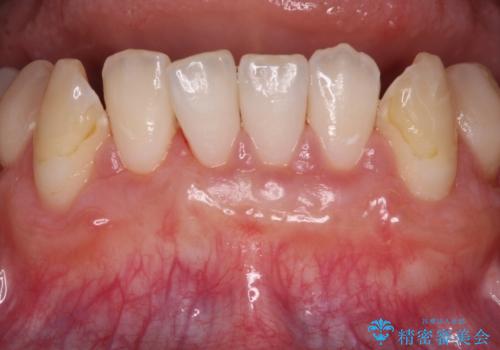

上顎両側から歯肉を採取したたため、術後は痛みや出血で辛い思いをされましたが、1回の処置で満足のいく結果となりました。

歯肉退縮に対して、上顎からの結合組織移植術(CTG)により、歯根の被覆を行うとともに、歯肉の厚みを増すことで将来の退縮リスクを抑制することとしました。